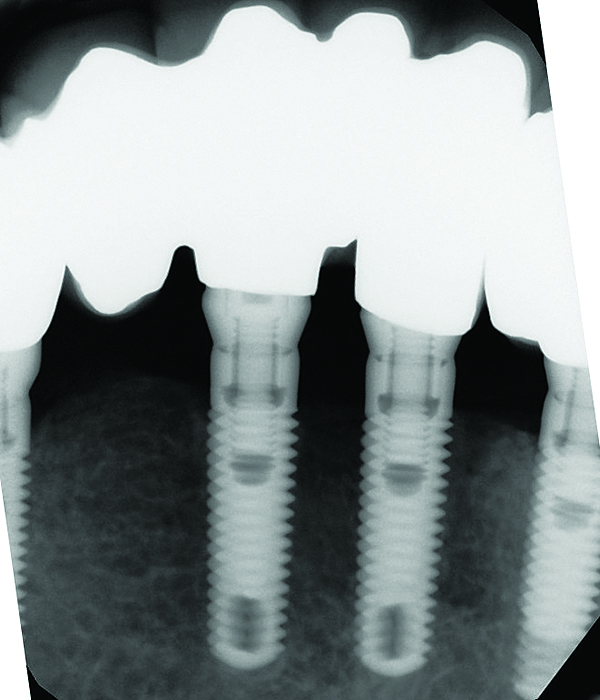

Fig 7 through Fig 14. Periapical radiographs of a 62-year-old woman who received a fixed porcelain-fused-to-metal reconstruction supported by abutments by internally connected dental implants. Fig 7 through Fig 10 are at initial prosthesis placement: mandibular site Nos. 30 and 29 (Fig 7); mandibular site Nos. 26, 25, and 23 (Fig 8); mandibular site Nos. 23 and 21 (Fig 9); mandibular site Nos. 21 through 19 (Fig 10). Fig 11 through Fig 14 are 11 years later (2013) and show excellent preservation of the vertical bone levels around the implants: mandibular site Nos. 30 and 29 (Fig 11); mandibular site Nos. 26 and 25 (Fig 12); mandibular site Nos. 25 and 23 (Fig 13); mandibular site Nos. 20 and 19 (Fig 14). It is interesting to note that in the mandibular right posterior quadrant there is a matched pair, ie, an external hex dental implant (No. 30) adjacent to an internally connected dental implant (No. 29). The bone levels around each of these designs are well-preserved at the 11-year follow-up.